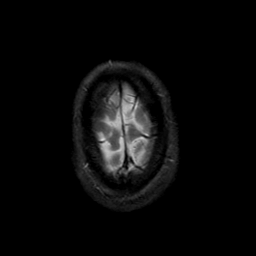

MR Study #21, November 3, 1991 -- Slice #46